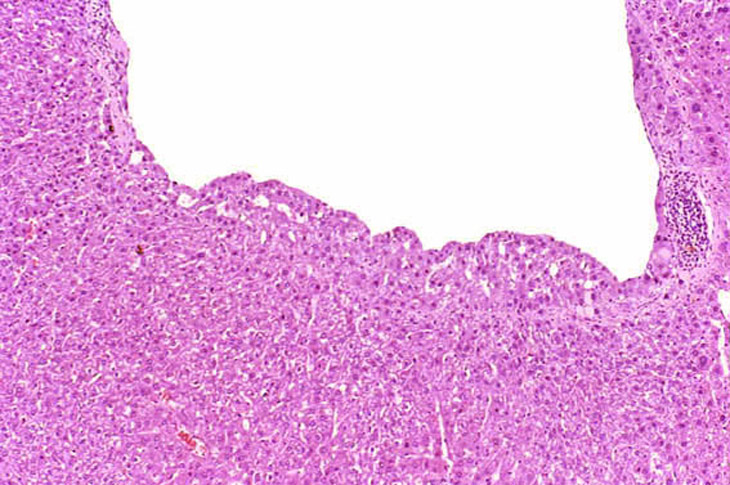

In some foci of cellular alteration, primarily basophilic foci, hepatocytes may occasional be seen to protrude into the lumen of hepatic veins. They are usually lined by a layer of flattened endothelial cells. This change has been considered by some to represent a form of microinvasion and such lesions have been diagnosed as hepatocellular carcinomas, possibly motivated by the fact that most are seen within foci induced by treatment with hepatocarcinogens. However, similar changes are occasionally seen in untreated mice and may not necessarily be associated with a focus of cellular alteration. Consequently, we cannot be certain that this change is actually a microcarcinoma. Two clusters of hepatocytes protruding into a large hepatic vein.